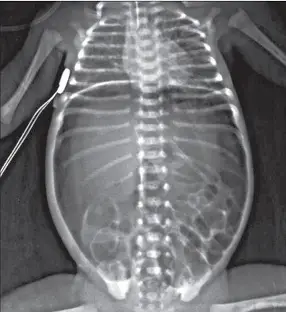

27週出生的早產兒,開始餵食12天後,突然發生嗜睡、腹脹、含膽汁嘔吐、糞便帶血絲等症狀。其腹部X光檢查如下圖。發生此狀況時,下列何種處置最不適當? 圖片描述

從正向仰臥腹部 X 光可見:

1. 多發、沿腸管壁排列之圓形至線狀透亮區,形成「double halo」或「soap-bubble」樣影,代表 pneumatosis intestinalis。

2. 右上腹肝實質內可見樹枝狀細小透亮影,符合 portal venous gas。

3. 未見跨膈或腹腔游離氣體,表示暫無明顯穿孔。

上述所見幾乎可確立 NEC 診斷,病程屬 Bell stage II~III。(pubmed.ncbi.nlm.nih.gov)